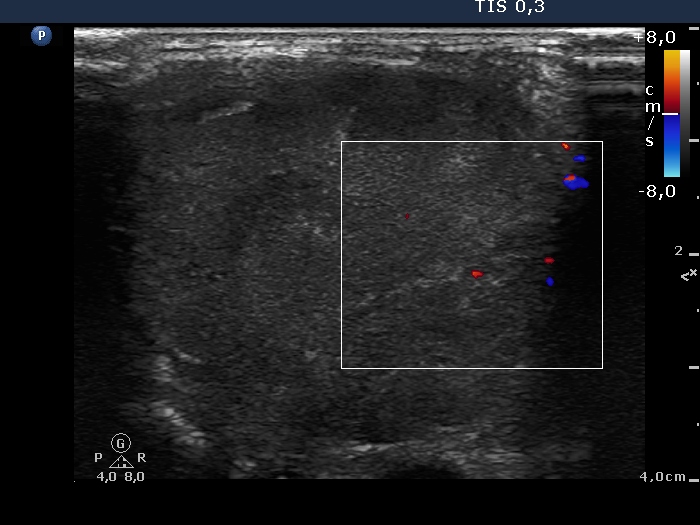

Clinical data: A 82-year-old man was referred for an evaluation of a rapidly increasing mass in the left thyroid. The tumor evolved over 3 weeks and caused palsy of the left recurrent nerve and dysphagia.

Ultrasonography revealed a hugely enlarged left left which was composed of multiple hypoechogenic, inhomogeneous nodules.

Cytological report: anaplastic cancer.

Histopathology disclosed anaplastic cancer.